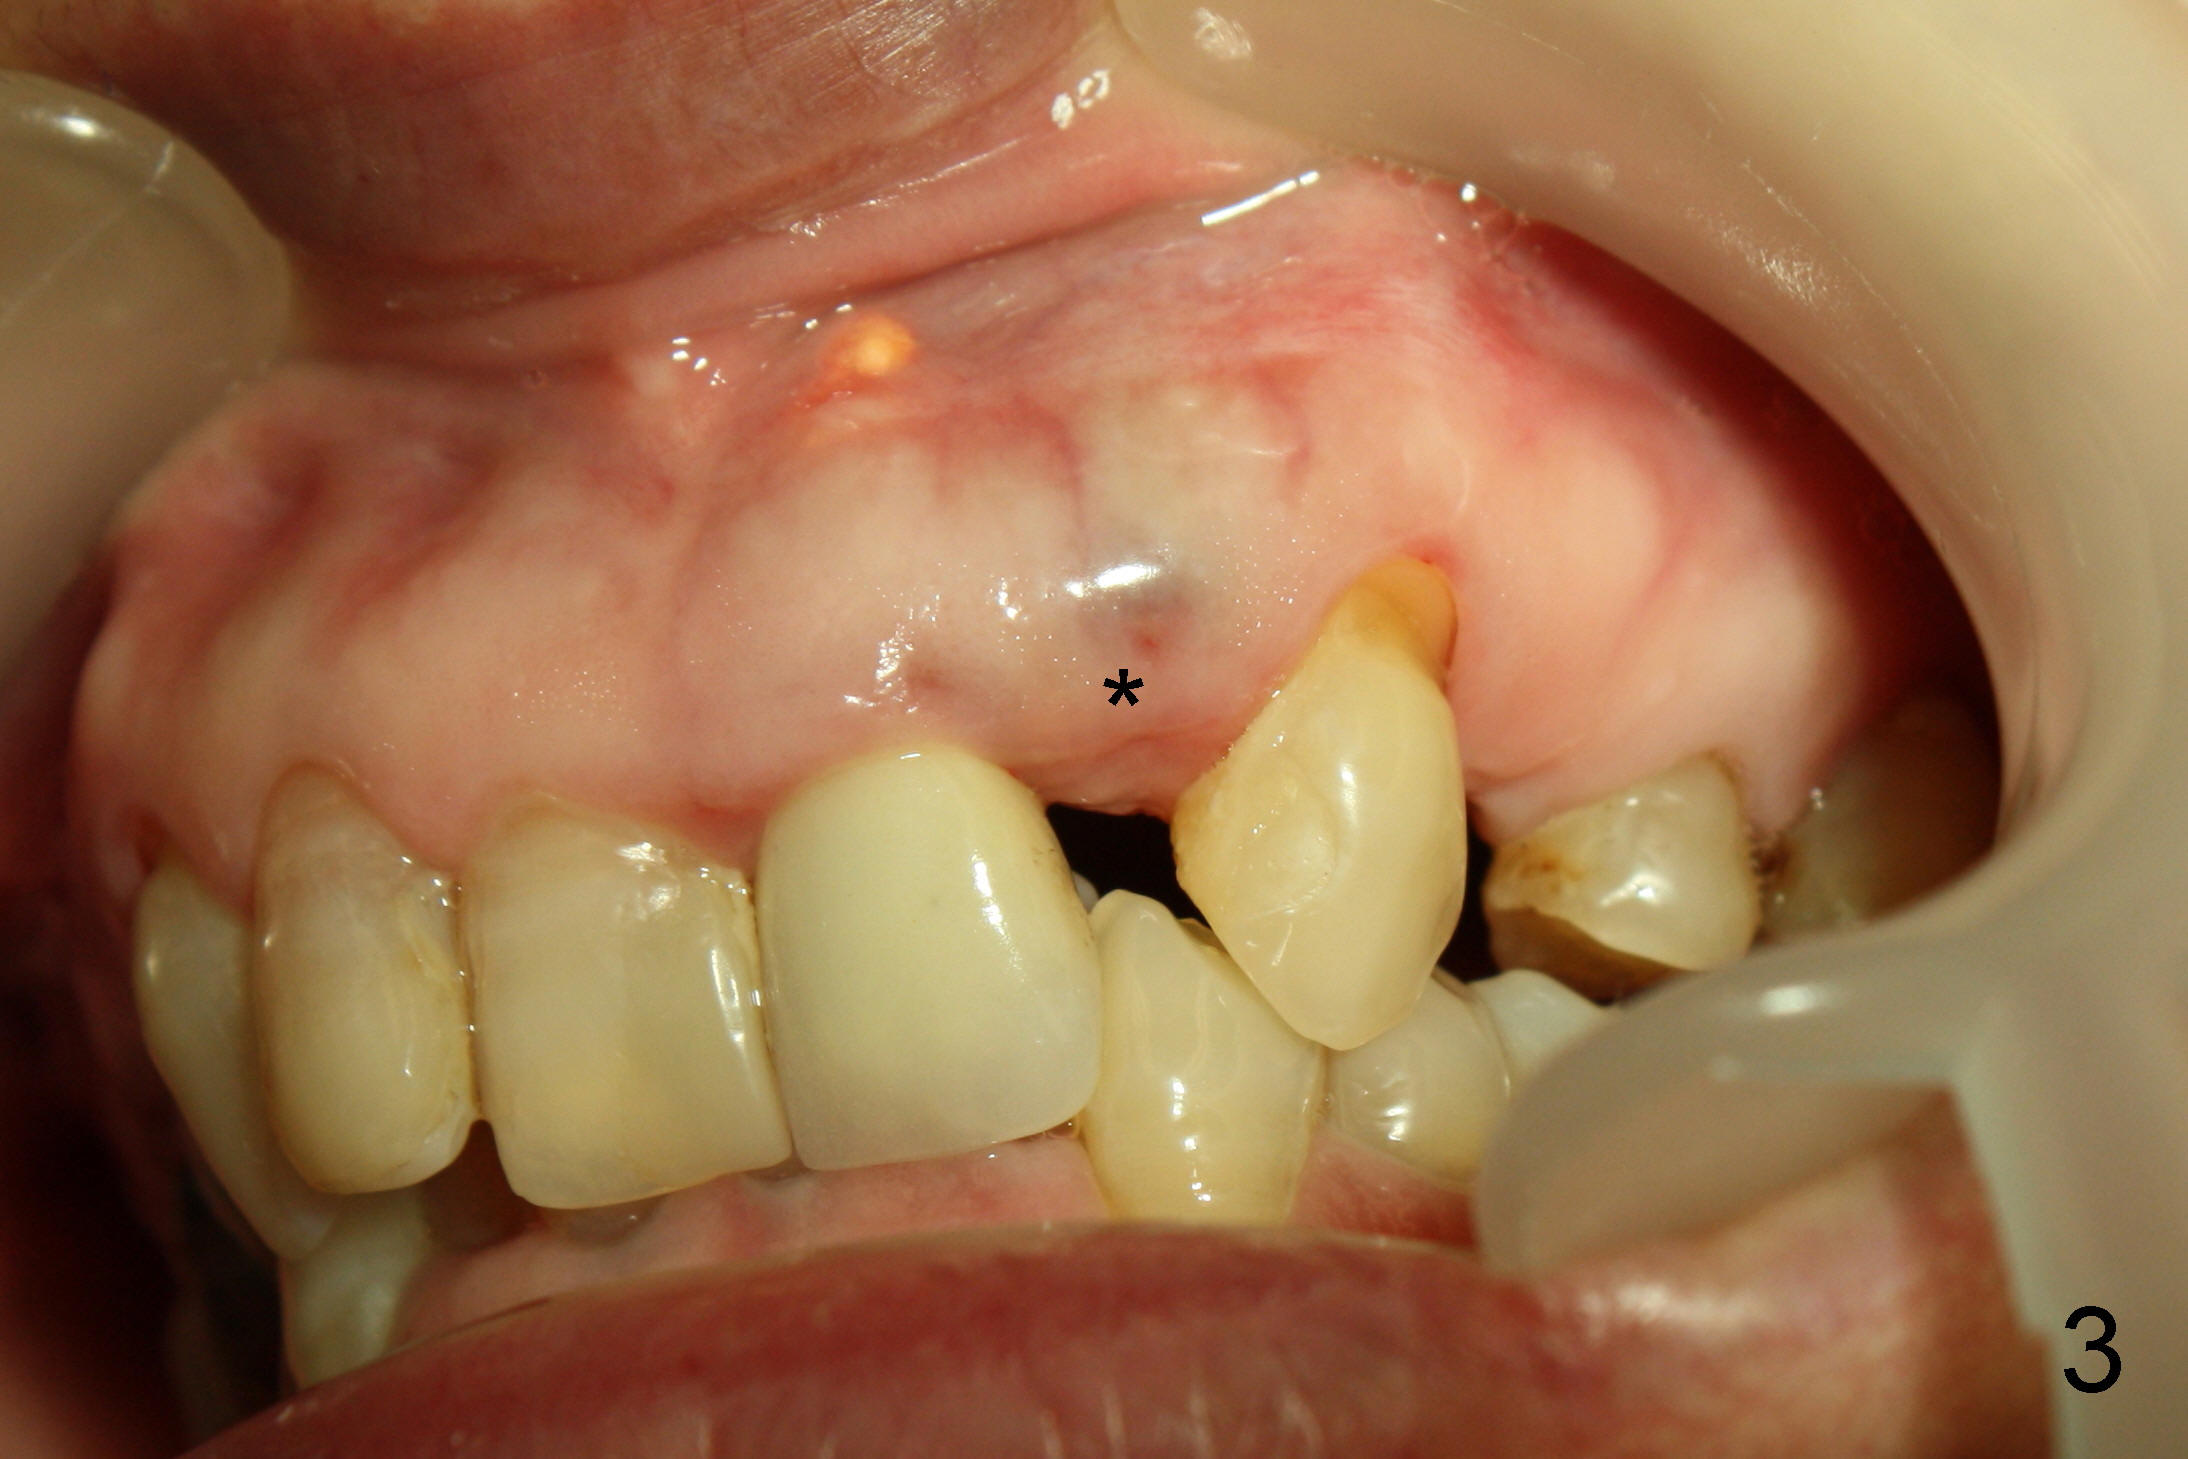

A fifty five year old lady requests implant restoration for the upper left lateral incisor after the crown fractures (Fig.3*). X-ray in Fig.1,2,4 were taken before loss of the crown. The biggest issue is the narrow space of this lateral mesiodistally (Fig.3).